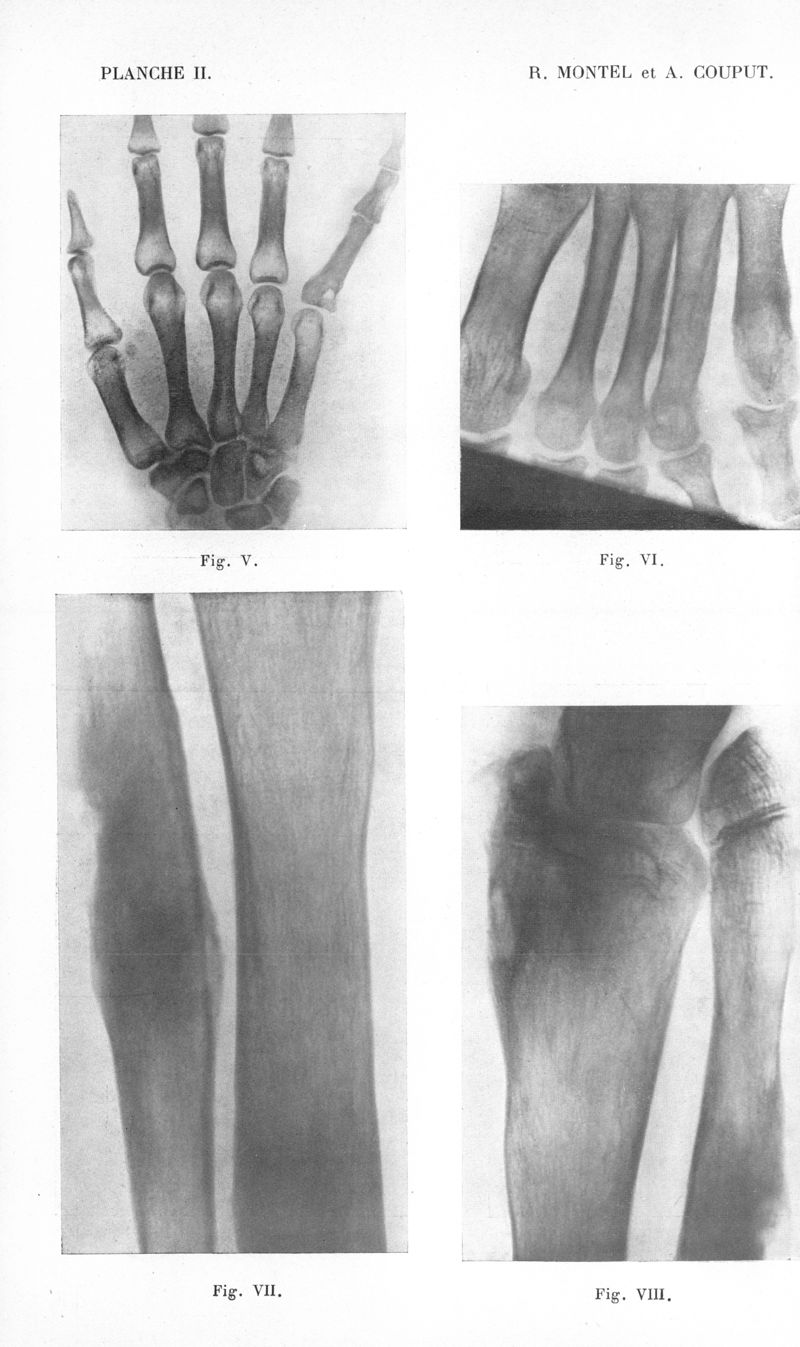

Bulletins de la Société de pathologie exotique et de ses filiales de l'Ouest africain et de Madagascar

1932, tome 25. - Paris : Masson, 1932.